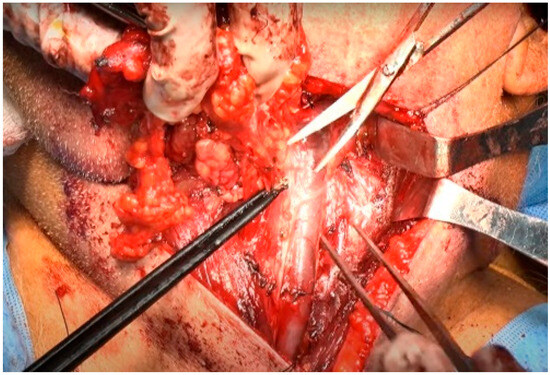

The IMA was accessed from the lateral pterygoid muscle by navigating through the space between the lateral and posterior walls of the maxilla and masseter muscle [8]. Buccal fat was removed either via direct electrocauterization or via ligation using hemostatic forceps and scissors. The lateral pterygoid muscle, located behind the temporalis muscle, was used as a landmark to locate the IMA, which was just above the lateral pterygoid muscle or below the inferior margin of the muscle (Figure 3) [9,10].

Figure 3.

Postmaxillary space. The white arrow shows the internal maxillary artery in the postmaxillary space. Z: zygoma; M: maxilla; F: buccal fat.